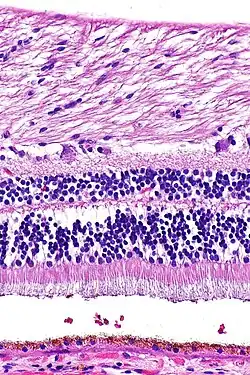

zunächst Ganglienzellen und deren Axone / grau: Innere plexiforme Schicht / Amakrine Zellen, Bipolarzellen, Horizontalzellen / gelb: Äußere plexiforme Schicht / Photorezeptorzellkörper / hellbraun: Außensegmente mehrerer Stäbchen und eines Zapfen

Ein Querschnitt der Netzhaut zeigt im Lichtmikroskop eine auffällige Schichtung, die durch abwechselnd zellkernreiche und -arme Lagen gebildet wird. Die Schichten besitzen charakteristische Zelltypen und subzelluläre Kompartimente. Die Nervenzellen der Netzhaut lassen sich in drei Gruppen gliedern:

Schichten der Netzhaut

Das durch die Pupille einfallende Licht durchdringt Linse und Glaskörper als transparente Medien und passiert dann mehrere Schichten der Netzhaut, bevor es von den Photorezeptorzellen des Neuroepithels detektiert wird, die dem außen anliegenden Pigmentepithel zugewandt sind. Vom Glaskörper her zur Aderhaut hin, also bezogen auf das Auge von innen nach außen, zeigt die lichtempfindliche Netzhaut einen schichtartigen Aufbau aus Zellkörpern im Wechsel mit Zellfortsätzen. Hierbei lassen sich meist zehn Schichten unterscheiden, im Bereich der Sehgrube des Gelben Flecks sind einige seitwärts verlagert.

Legende linkerseits:

RPE retinales Pigmentepithel

OS Außensegmente der Photorezeptorzellen

IS Innensegmente der Photorezeptorzellen

ONL äußere nukleäre Schicht

OPL äußere plexiforme Schicht

INL innere nukleäre Schicht

IPL innere plexiforme Schicht

GC Ganglienzellschicht

Legende rechterseits:

BM Bruch-Membran, P Pigmentepithelzelle

R Stäbchen, C Zapfen

Pfeil: Membrana limitans externa

H Horizontalzelle, Bi Bipolarzelle

M Müller-Zelle, A Amakrinzelle

G Ganglienzelle, Ax Axone

Lichteinfall von innen (unten, GC) nach außen (oben, RPE)